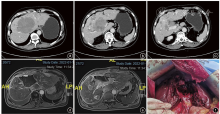

图1. 一例NETLM外科减瘤术前术后影像学检查及术中图像 注:a、b、c为术前增强CT,示肝内多发转移灶;d、e为术后增强MRI复查,示减瘤大部分病灶,剩余肝脏代偿增大;f为术后肝脏断面;NETLM为神经内分泌肿瘤肝转移